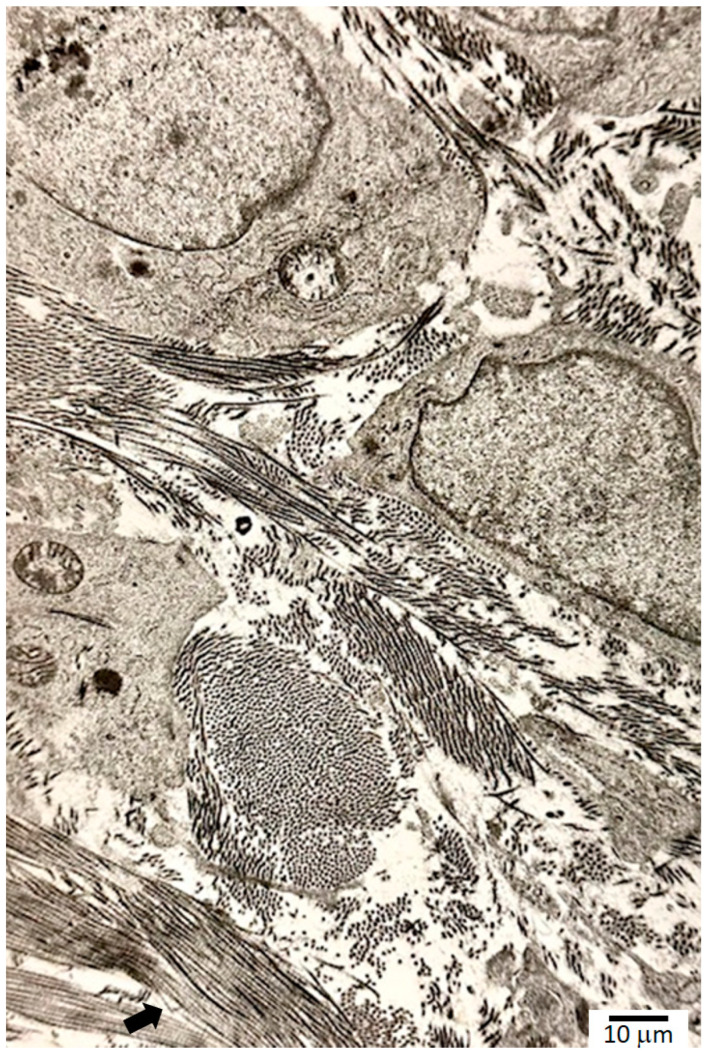

Fibroblasts, differentiated from local stem cell pools such as small pericytes, appear in the wound by the second to fourth day, with detectable collagen synthesis by day 4 to day 6 (Figure 2). Histamine and tryptase from MCs stimulate fibroblast synthesis and the release of SCFs and FGFs. SCFs recruit more MCs and induce MCP-1. MCP-1 increases transcription of α1(I) of collagen type I. By the end of week 1, the collagen production rapidly increases, until the middle part of week 3 (day 17), with minimum increase after that, returning to nominal levels by the end of week 6 in the normal healing process. Collagen undergoes extensive post-translational modifications, involving hydroxylation of proline and lysine residues and the formation of covalent cross-links. Proline residue, or prolyl, hydroxylation requires proline-4-hydroxylase, a member of the alpha-ketoglutarate-dependent hydroxylases located in the endoplasmic reticulum, with ferrous ion, Fe2+, as a cofactor and vitamin C as an electron donor to prevent the oxidation of iron from the ferrous to ferric state [ref. 36]. Molecular oxygen is the source of oxygen in proline hydroxylation. From these two crucial but opposing roles, the importance of tightly regulated oxygen levels is clear: normal healing cannot occur with too much or too little oxygen. The oxidative deamination of the epsilon amino group of the lysine residues forms aldehydes, which is another important site for covalent cross-links while regenerating the aldehyde group. Lysyl amino oxidase, with copper as a cofactor, catalyzes this reaction. 4-hydroxyproline is exclusively present in collagen, making up 9% of the molecule with proline contributing 12% and glycine 35% [ref. 37].

During the remodeling process, wound contracture occurs through the action of myofibroblasts. Myofibroblasts exert their contractile forces by focal adhesion complexes that link the intracellular elements such as the cytoskeleton to the ECM. Early scars appear pinkish red due to their dense capillary networks; regression of these capillaries allows scars to lighten significantly over time. Ultimately, the formation of a mature scar marks the end of the remodeling phase (Figure 3). In addition to a collagen pattern distinctly different from native skin, epidermal appendages such as pilosebaceous complexes are lacking in mature scars [ref. 45].